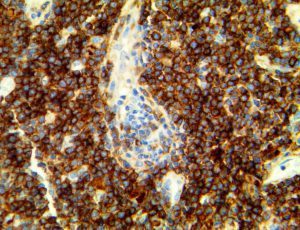

It is the ICU physician who is most likely to witness one of the deadliest manifestations of the abnormal immunological response, the cytokine storm syndrome (CSS). This response is also referred to by some as the cytokine release syndrome (CRS). CSS is characterized by continuous activation and expansion of macrophage and lymphocyte populations, which secrete large amounts of cytokines, causing the cytokine storm. This massive cytokine release is akin to hemophagocytic lymphohistiocytosis (HLH) disease, a syndrome characterized by initial unchecked and persistent activation of cytotoxic T lymphocytes and NK cells.

Clinical and laboratory manifestations of HLH include fever, enlarged liver and/or spleen, neurologic dysfunction, coagulopathy, liver dysfunction, cytopenias (i.e., low levels of erythrocytes, leukocytes, and/or platelets), hypertriglyceridemia, hyperferritinemia, hemophagocytosis, and eventually diminished NK cell activity as the immune system becomes progressively paralyzed. HLH can be familial (primary HLH) or secondary to another disease process (sHLH), such as rheumatic disease, in which it is referred to as macrophage activation syndrome (MAS, characterized by elevated ferritin).